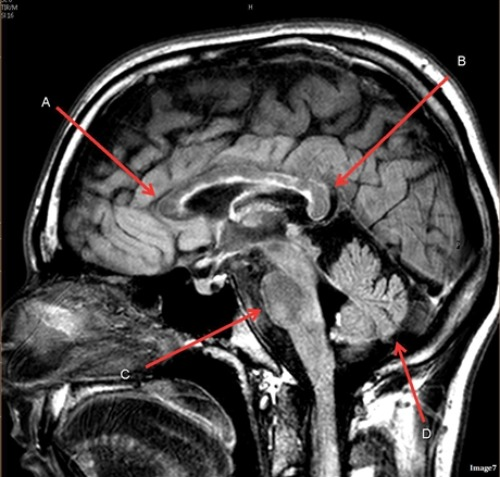

Letter D in Image 7 is pointing to:

A. Pons

B. Cerebellum

C. Hypothalamus

D. Genu of the corpus callosum

E. Splenium of the corpus callosum

Letter A in Image 7 is pointing to:

Letter B in Image 7 is pointing to:

Letter C in Image 7 is pointing to:

Image 7 is an example of a _____ weighted sequence acquired in the ______ scan plane.

A. T1; Axial

B. T2 FLAIR; Sagittal

C. T2; Axial

D. T2; Sagittal